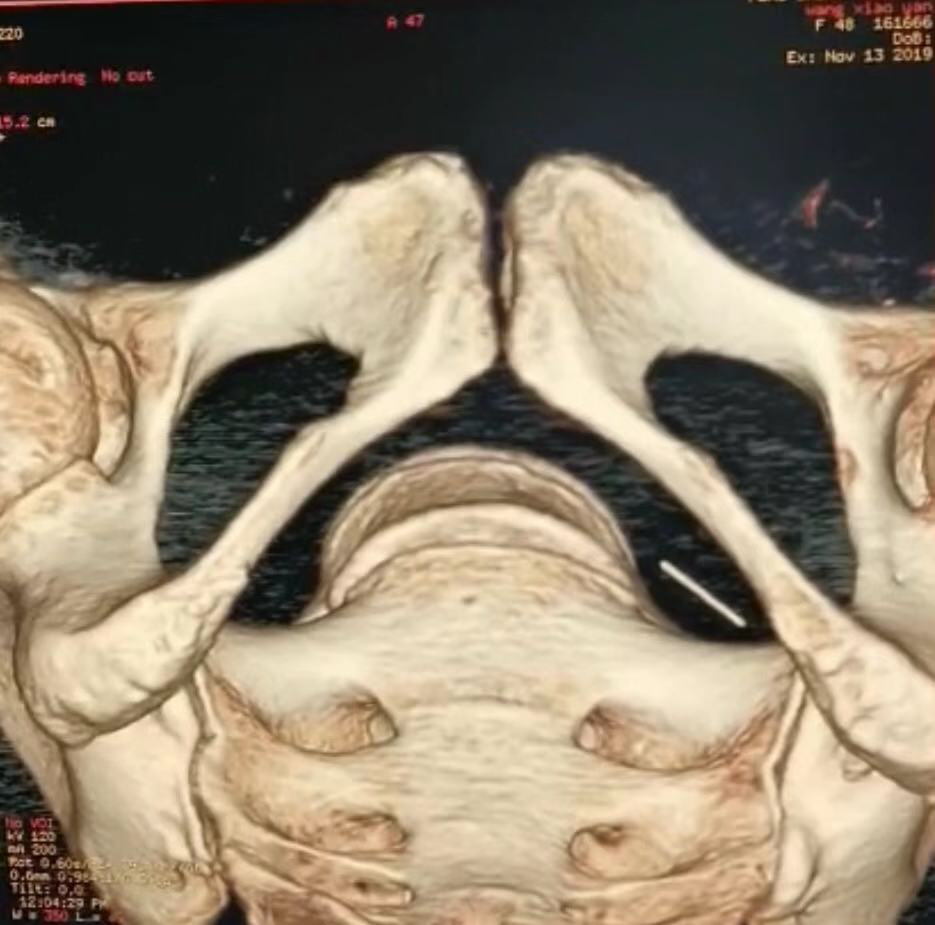

几经周折,她来到西安凤城医院妇科,经CT三维重建检查提示这枚细小的针位于盆腔左侧闭孔内肌邻近脂肪间隙内。经体表和阴道根本无法触摸到,怎样取出呢?太少见了,以前的学术上根本没有这方面的经验。如果采用切开皮肤皮下等组织去找,无疑会创伤很大,有出血、感染、伤口不愈合、瘢痕等风险,而且定位困难,犹如大海捞针。妇科谢拥军主任就把情况发到医院的微信平台上,让大家集思广益,一定要帮患者解决问题,连院长都参与了想办法,出主意。最终,普外胸外科王东君副主任提出一个办法,大家都拭目以待,能成功吗?

在介入手术室,准备物品,给患者麻醉、摆放体位、防护,一阵忙活后,谢拥军主任、王东君副主任等医生护士都穿上铅衣,打开介入手术用的显像设备,可以清楚的显示一根细细小小的针头就在患者体内,王东君主任用一根长约9cm的骨科穿刺针从阴道内穿入到达针头遗失的附近,拔出针芯,寻找目标,大家都屏息敛声,接近了,更接近了,没有进去,眼看着碰上了,还是没进去……大型C型臂下的成像呈二维平面的,无法进行适时的三维成像,反复调试C臂,针头和针套还不在一个平面,“还差一点、还差一点”,王东君副主任不停的调换角度,针套也不停的变换方向追寻针头,时间一点一点过去了,已经快18:00了,就在大家丧失信心准备更换第二套方案时,针套终于将针头捕获,微针被完全的套入针套内。